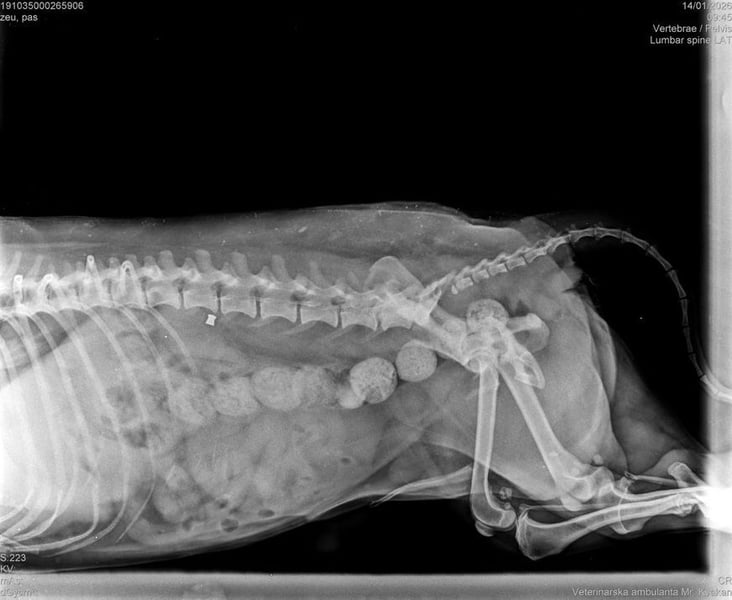

Die medizinische Untersuchung ergab, dass außer einem Schrecken, keine Verletzungen festzustellen waren. Auch die Röntgenaufnahmen bestätigten diese Diagnose.